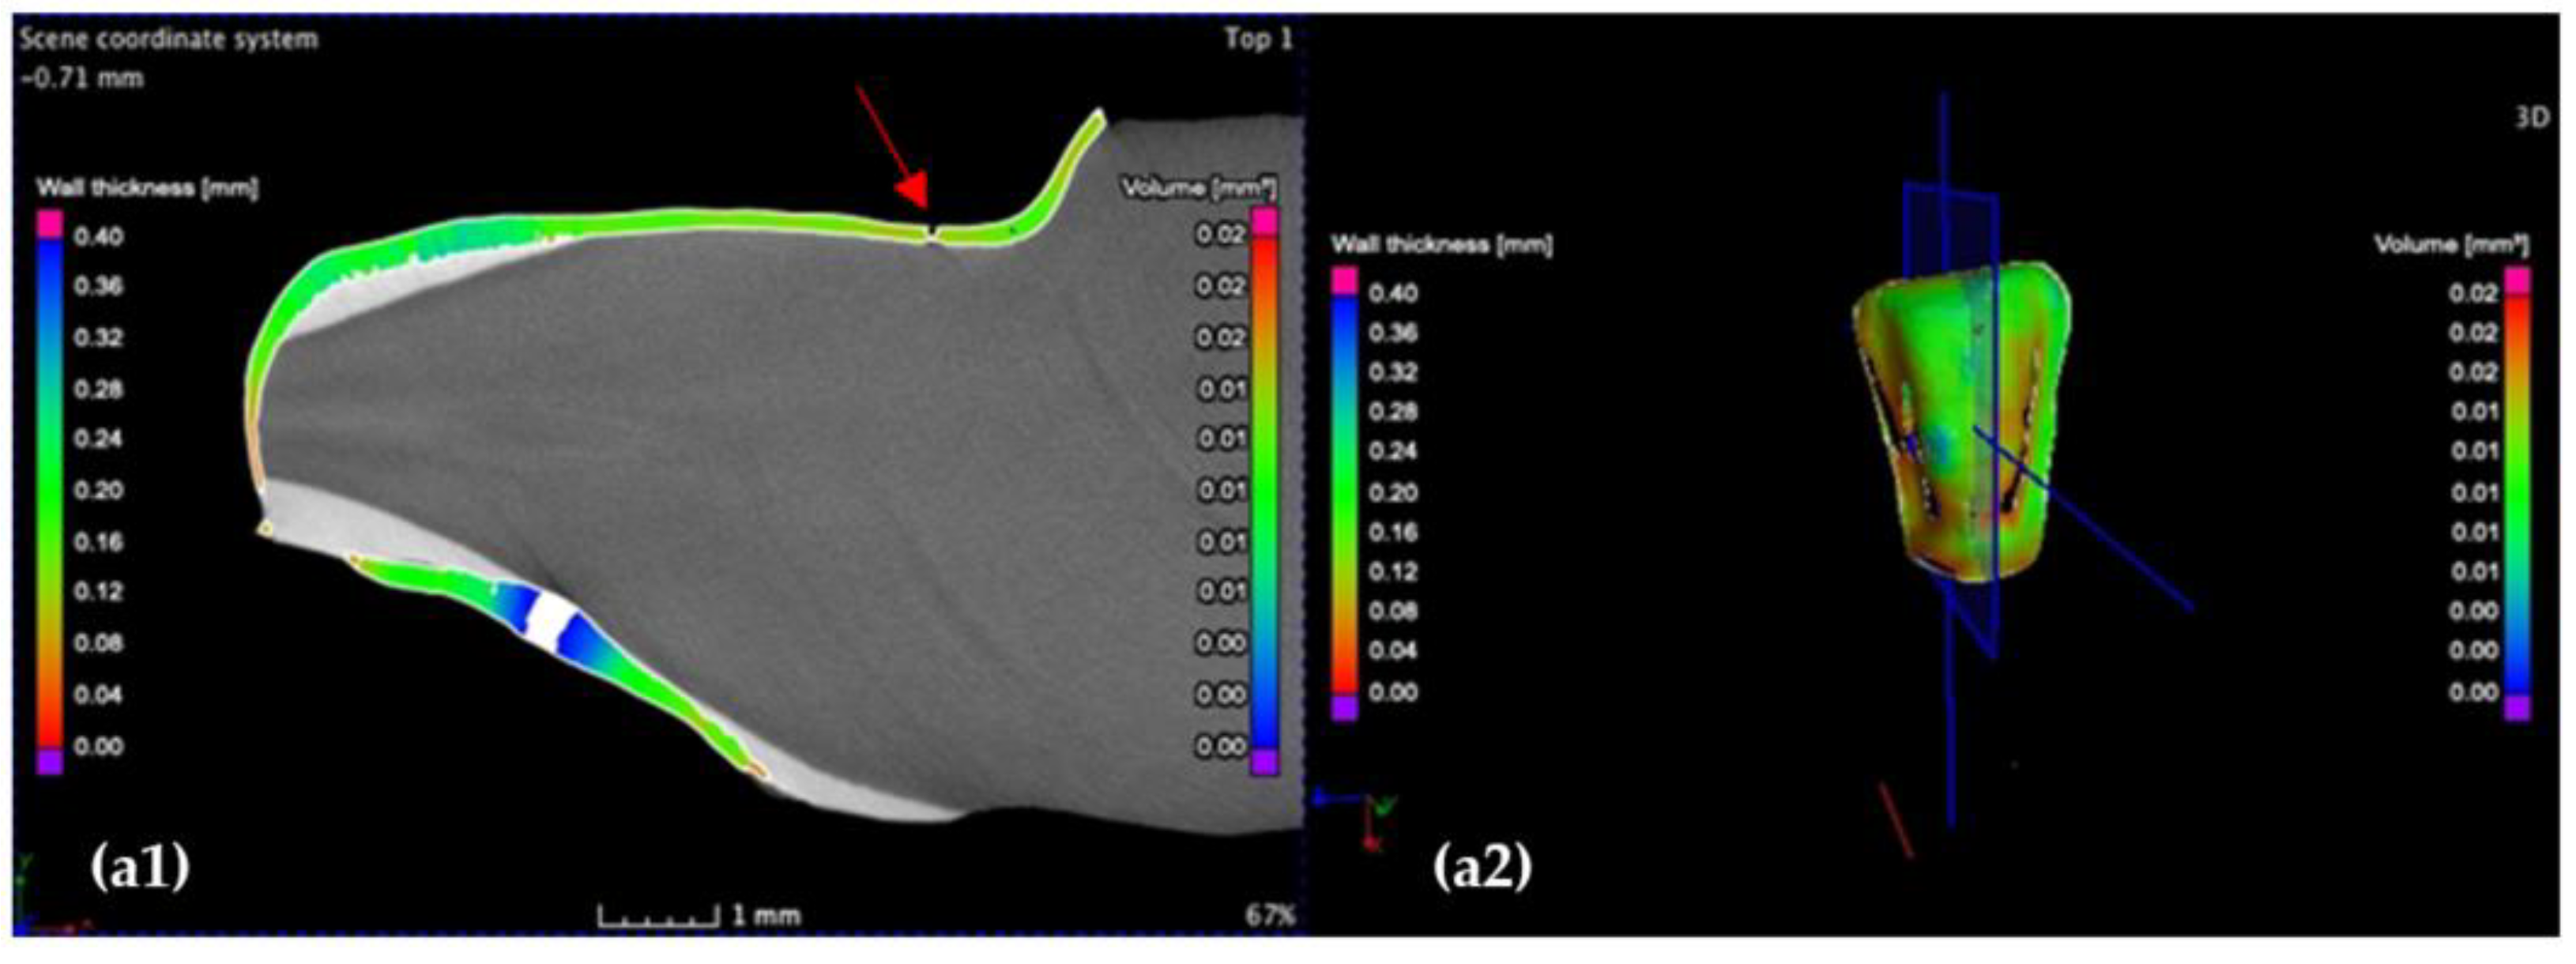

3.2. Micro-CT

3.3. Mathematical Modeling of the Micro-CT Results